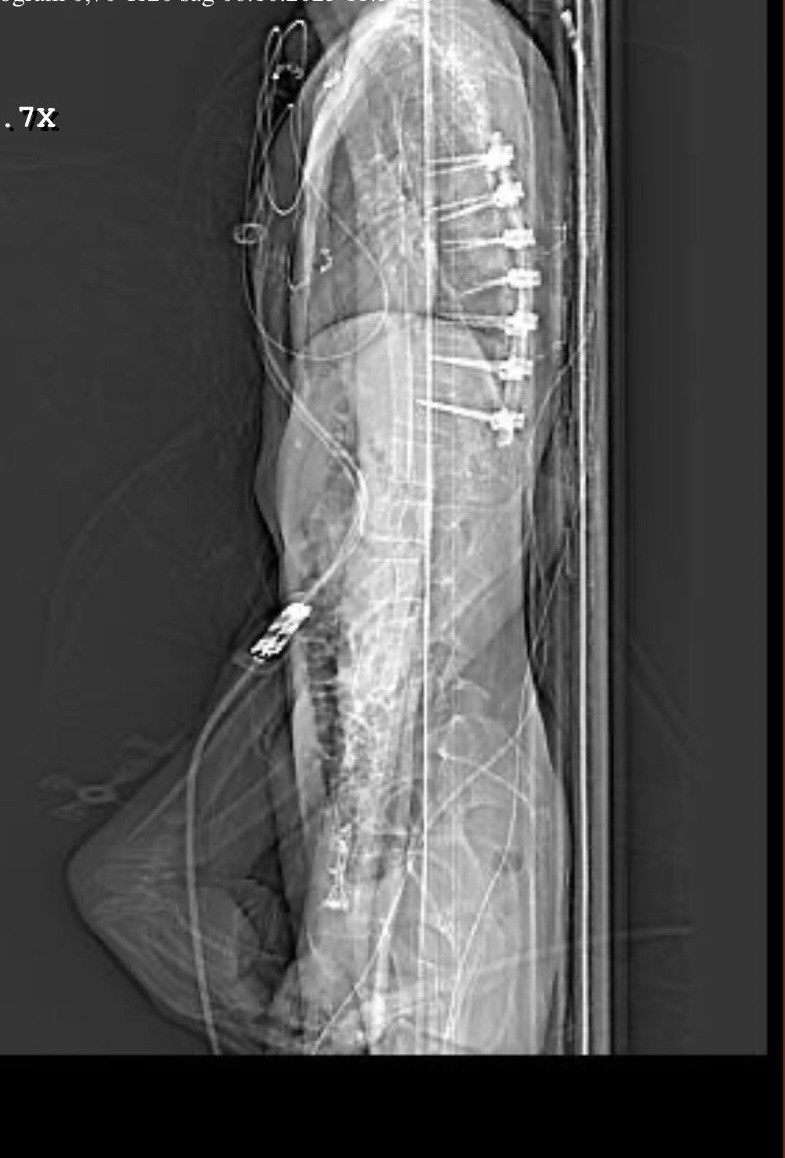

"Beş gün entübe edildi. Ne olacağı belli değildi çıkmama ihtimali vardı. Şükürler olsun doktorlarımız ve Rabbim sayesinde entübeden çıktık. Hatta ciğerin birisinde infilak vardı; ciğer sorunumuzdan dolayı özellikle yoğun bakımda entübediydik. Beş günün sonunda ciğerleri toparlamaya başladı; entübeden çıkarttılar. Solunumu normale döndü. Sırayla sağlığı yerine gelmeye başladı. Bir hafta sonra kolundan ameliyat oldu platin koydular. Omurilikten ameliyat olduk. Omuriliğinde ilk röntgende tek kırık gördüler; üç kemiği birbirine bağlayacaklardı. Sonradan ikinci röntgende üç kırık olduğunu gördük; yedi kemiği birbirine bağladılar. Omuriliğe platin takıldı. 14 tane civatamız var. Şükürler olsun doktorlarımıza, Allah razı olsun. Evladımız gayet iyi, sağlıklı, yerinde. Artık işte suratta, çenede, burunda, elmacık kemiklerinde parçalı kırıklarımız var. Osman Gazi Fakültesi'nde Allah'ın izniyle buradaki hocalarımıza, önce Rabbim'e sonra hocalarımıza emanet çocuğumuz. İnşallah daha iyi olacağız; ben kendi adıma söylüyorum. Çocuğuma, her motora bindiklerinde sürekli kask ve montlarını giymelerini tembihliyordum. Giymediklerinde fırça atıyordum. Eskişehir'de birçok yerde tanınırız, tanırlar. Sevenimiz, eşimiz, dostumuz çok; uyarırlar, telefon gelir, haber verirler. Her duyduğumda, gördüğümde söylerim. Sağ olsun, çocuğum da o gün beni dinlemiş, kaskını takmış. Şükürler olsun ki takmış; takmasaydı o gün, o kazada belki çocuğumuzu kaybederdik."